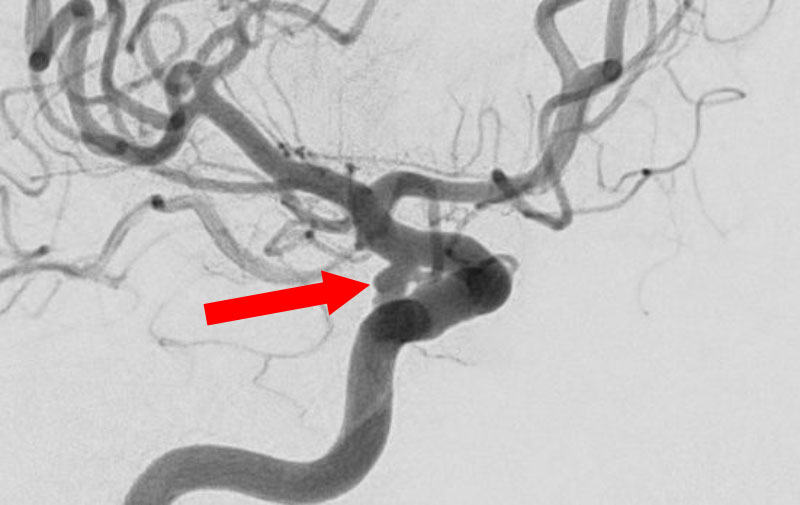

No.1631 手術後